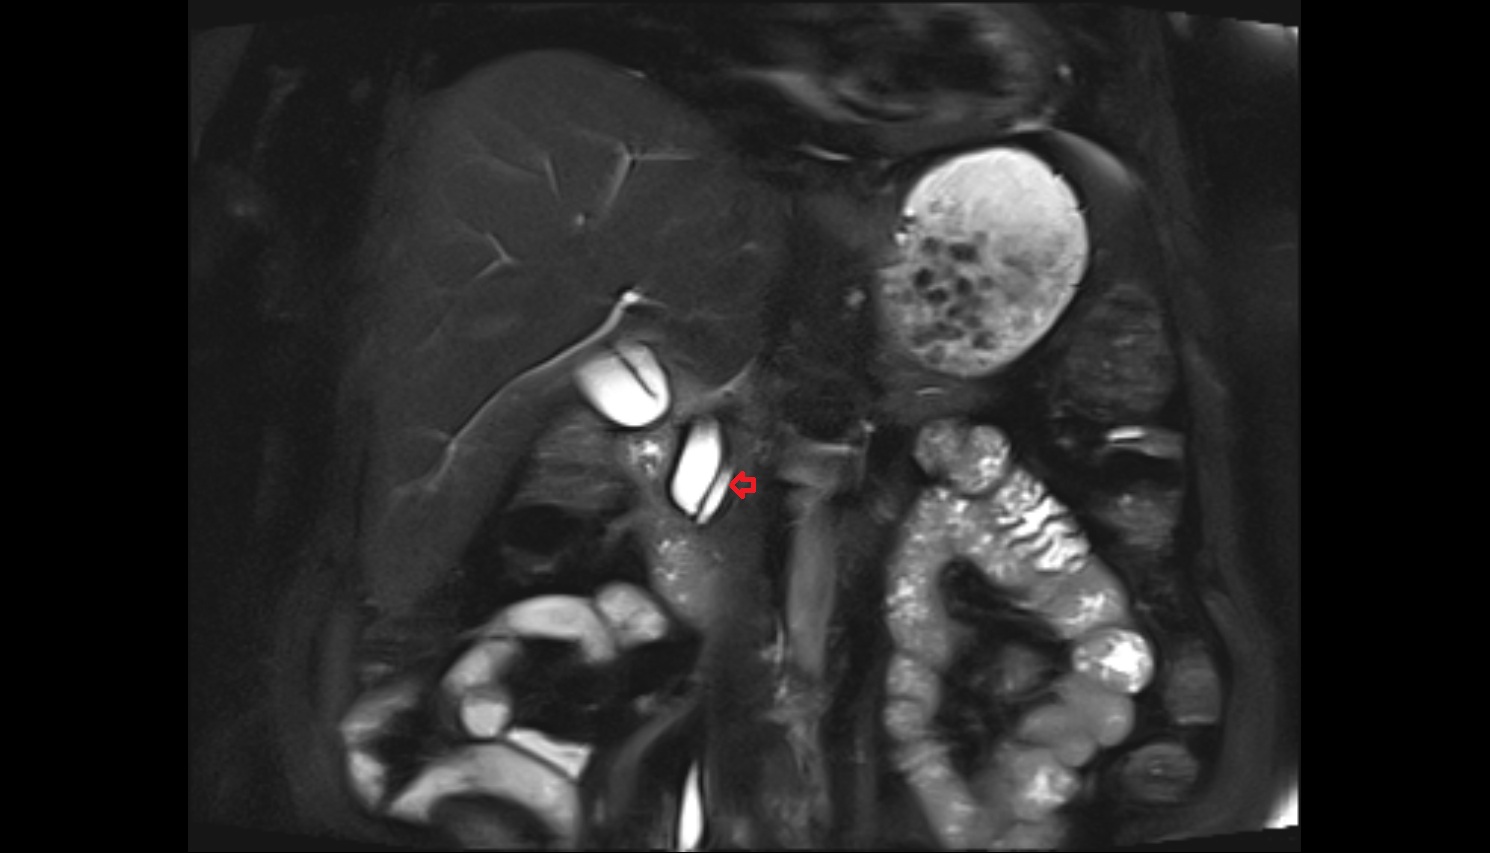

- Placenta

- Uterus (pregnancy)

- Amniotic fluid

- Umbilical cord

- Urinary Bladder in Pregnancy

- Cervix in Pregnancy

- Vagina in Pregnancy

- Fundus of uterus in pregnancy

- Fetal brain

- Fetal caudate nucleus

- Fetal thalamus

- Fetal pons

- Fetal cerebellum

- Fetal occipital lobe

- Fetal temporal lobe

- Fetal parietal lobe

- Fetal frontal lobe

- Fetal third ventricle

- Fetal fourth ventricle

- Fetal lateral ventricle

- Fetal superior sagittal sinus

- Fetal straight sinus

- Fetal transverse sinus

- Fetal sigmoid sinus

- Fetal cervical spine

- Fetal thoracic spine

- Fetal lumbar spine

- Fetal spinal cord

- Fetal Eyes

- Fetal paranasal sinuses

- Fetal tooth buds

- Maternal ovaries

- Fetal shoulder

- Fetal lungs

- Fetal Ribs

- Fetal trachea

- Fetal Heart

- Fetal aorta

- Fetal upper arm

- Fetal knee

- Fetal ankle

- Fetal foot

- Fetal thigh

- Fetal Lower Leg

- Fetal forearm

- Fetal Liver

- Fetal small bowel

- Fetal hand

- Fetal urinary bladder

- Fetal kidneys

- Fetal rectum

- Fetal elbow

- Fetal wrist

- Fetal hip

- Fetal anus

- Fetal Fingers

- Fetal buttock

- Fetal scrotum

- Fetal testis

- Fetal penis

- Fetal colon

- Fetal stomach

- Fetal spinal canal